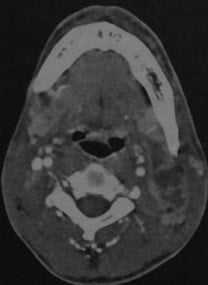

Септический гранулематоз у мужчины 27 лет. КТ с контрастированием: крупный округлый абсцесс с интенсивным усилением стенки, расположенный позади левой грудино-ключично-сосцевидной мышцы. Плотность в полости абсцесса снижена, выявляются перегородки.

КТ с контрастированием: занижнечелюстной абсцесс на уровне угла нижней челюсти слева с множественными внутренними перегородками. Наблюдается характерное снижение плотности в центре абсцесса (жидкость) и усиление стенок. Отек тканей, окружающих абсцесс.